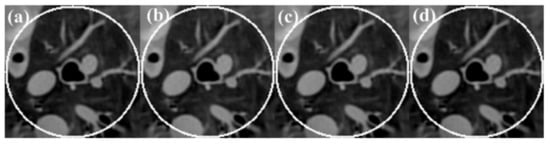

To investigate the effect on the accuracy of an estimated DC value on the recovery of an intensity drop, the reconstructed ROIs from the normal-dose sinogram with four different DC values near the true value are shown in Figure 10. The corresponding central horizontal and vertical profiles are shown in Figure 11. It can be seen that the proposed algorithm is robust with respect to the DC value.

Figure 10.

Reconstruction results with different DC: (a) DC = 2900; (b) DC = 3000; (c) DC = 3100; (d) DC = 3200. The display window is [−700 800]HU.